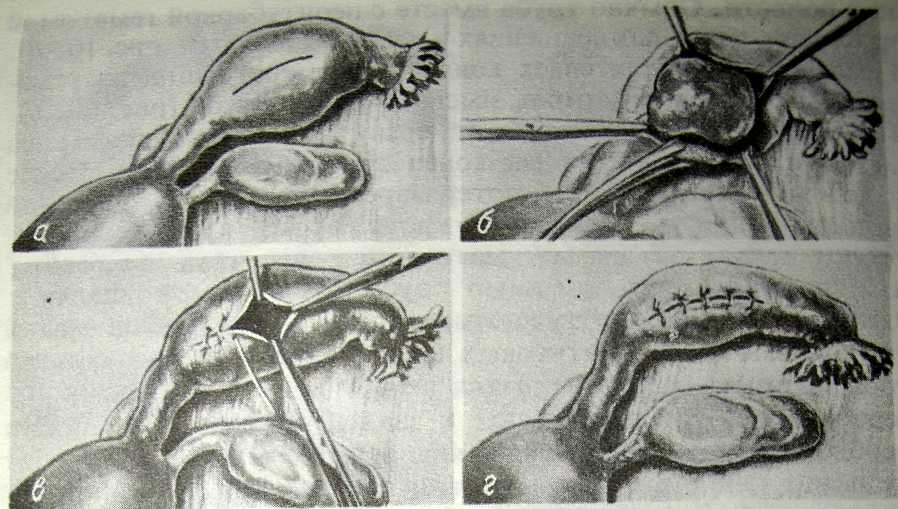

Заблуждения и факты о внутрибрюшной беременности